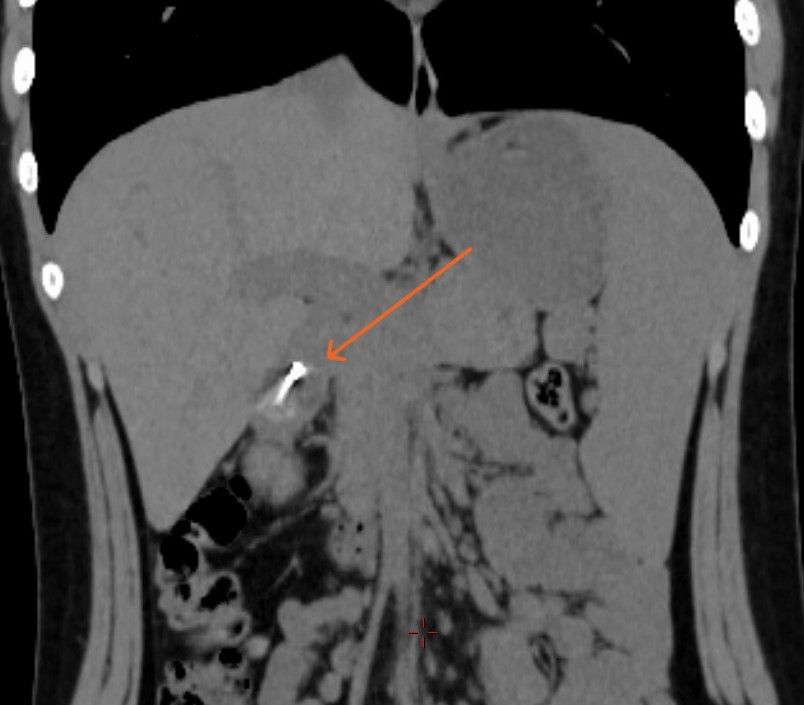

經過電腦掃描(CT),一條長約1.9厘米的針狀異物已到達其胃部與十二指腸之間。由於針尖極為鋒利,隨時可能刺穿消化道,引發致命的腹膜炎。由於小劉胃內仍有大量未消化的食物,而進行全身麻醉內窺鏡手術,按規定須禁食至少六小時;其次,他年紀尚輕,胃部發育未全,麻醉期間出現吸入性肺炎的風險遠高於成年人。